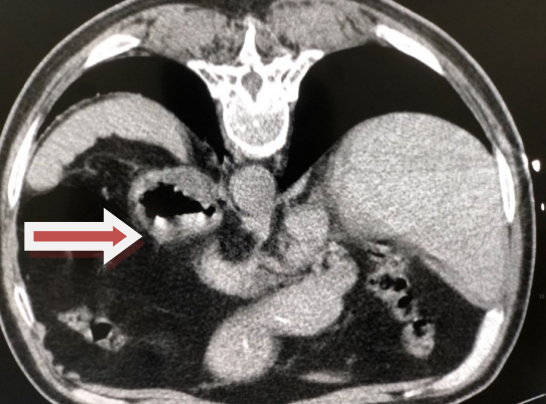

入院后,在做完相應(yīng)的術(shù)前準備后,患者接受了介入治療。此次手術(shù)是在CT引導(dǎo)下進行的,經(jīng)皮腎囊腫穿剌抽吸硬化介入治療。躺在CT檢查床上,可以看出患者還是有些緊張的。

囊腫已明顯縮小,最終會完全消失